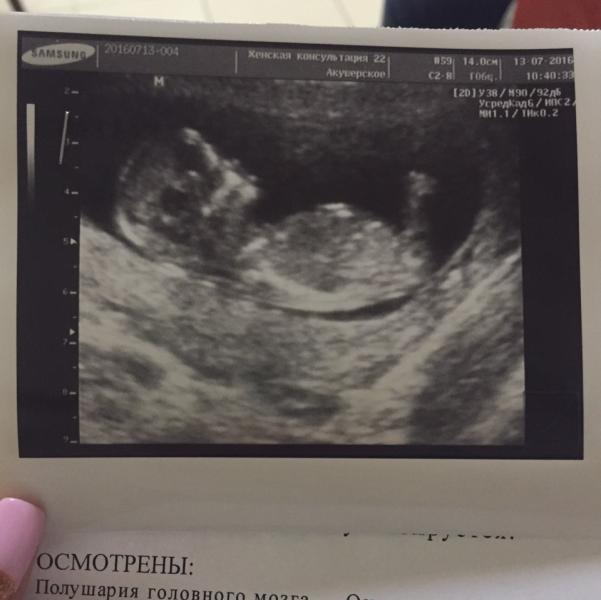

Хотела коротко рассказать свою историю похода в ЖК номер 22 на пр.Просвещения) на первый скрининг 😀

Ох,как я переживала за то,что первый скрин самый важный,за то,что иду не в частную клинику,а в гос.учреждение...

Как оказалось,переживала напрасно 😊 с моим малышом все в порядке 💕 приём занял примерно минут 13,но! Я считаю,что этого времени достаточно. Узист все очень быстро замерила и все комментировала (для меня это важно! А то обычно все из них вытаскиваешь клещами)...